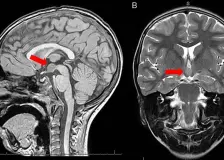

Alexanderova choroba – co je to: příznaky, příčiny a léčba

Alexanderova choroba je vzácné genetické onemocnění nervového systému, které postihuje bílou hmotu mozku a myelin. Nejčastěji ji způsobuje změna v genu GFAP, která narušuje funkci podpůrných buněk nervové tkáně. Mezi příznaky patří opožděný vývoj, epileptické záchvaty, zvětšený obvod hlavy, poruchy řeči, polykání, koordinace a chůze. Léčba je převážně podpůrná a zaměřuje se na zmírnění příznaků, Continue Reading The post Alexanderova choroba – co je to: příznaky, příčiny a léčba first appeared …